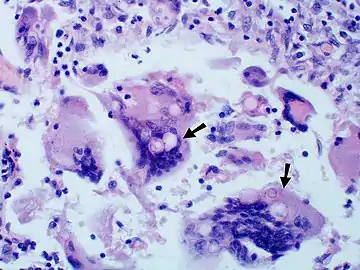

Large, broadly-based budding yeast cells characteristic of Blastomyces dermatitidis in a GMS-stained biopsy section from a human leg.

Once suspected, the diagnosis of blastomycosis can usually be confirmed by demonstration of the characteristic broad based budding organisms in sputum or tissues by KOH prep, cytology, or histology.[27] Tissue biopsy of skin or other organs may be required in order to diagnose extra-pulmonary disease. Blastomycosis is histologically associated with granulomatous nodules.